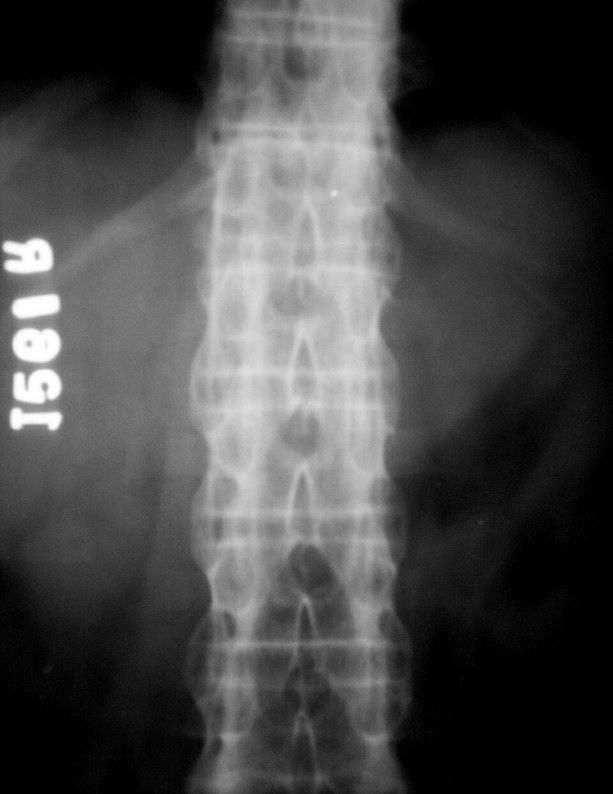

A S Bamboo spine 3